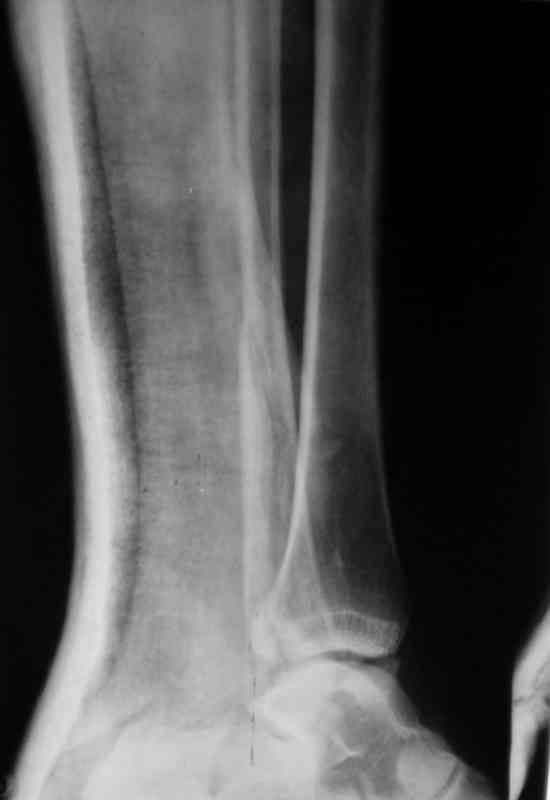

Вот рентгенконтроль на 7-е сутки после репозиции.

Серега, привет! А что наш ув.доцент А.П.М. говорит по этому поводу. И вообще, я не знал, что ты лечишь 3-хлодыжечные задними лонгетами, - нас с тобой учили это делать циркулярными гипсовыми повязками. Все равно, удачи! На контроле, почему-то, все заманчиво хорошо. Не спеши делать выводы

Стандартными снимками считается прямая, боковая и мортиз!!!, а так трудно гадать, насколько потеря длины малоберцовой. На боковом снимке не сопоставленный перелом медиальной лодыжки и перелом заднего края без смещения.

Трехлодыжечные переломы относятся к нестабильным переломам, при вовлечении перелома заднего края больше 15% суставной поверхности и смещения более 2 мм тогда такие переломы необходимо оперировать.

Трудно удержать трехлодыжечные переломы задней лонгетной повязкой (на снимке), а последующие долгие гипсовые повязки могут привести к контрактурам.

Очень жаль, что Вы так считаете и не прислушались к мнениям уважаемых коллег. Проблема этого голеностопного сустава не в "висячей" внутренней лодыжки, а ротированной и, возможно, укороченной малоберцовой кости. На снимках подвывиха как-буд-то бы нет, но таран ротирован и это в дольнейшем будет причиной раннего артроза.